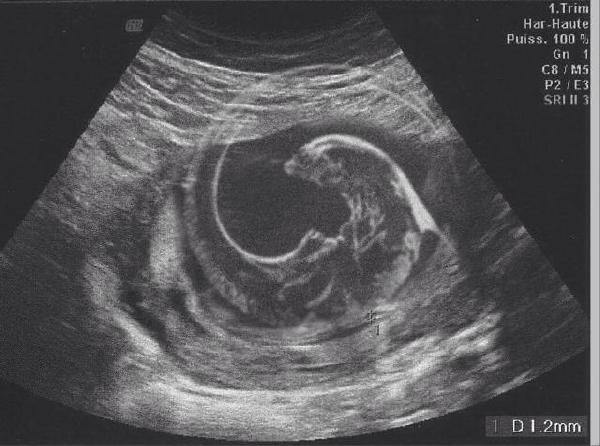

大家帮我看看胎儿情况怎么样

大家帮我看看胎儿情况怎么样.jpg

(41.68 KB)

2020-5-9 10:24

异形[76] [76] [76]